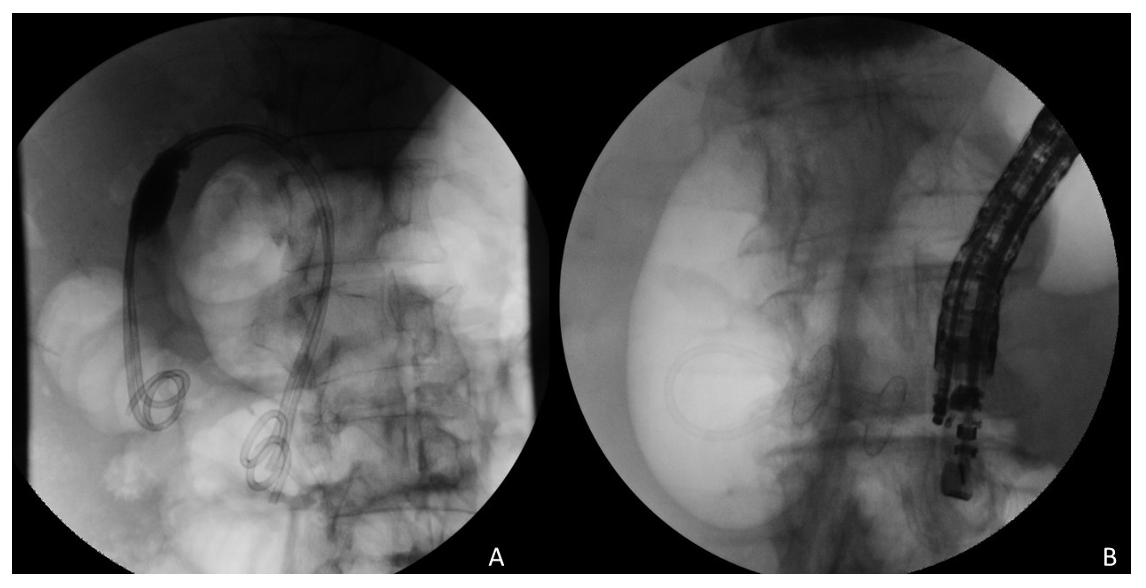

From www.researchgate.net

Intraoperative ERCP fluoroscopic images demonstrating no cystic duct or Ercp Without Gallbladder Endoscopic retrograde cholangiopancreatography (ercp) is an invasive procedure used for the diagnosis and treatment of obstruction in the biliary system. Learn how to prepare, what to expect, and what are the risks of ercp from the national institute of diabetes and digestive and kidney diseases (niddk). Endoscopic retrograde cholangiopancreatography (ercp) is a combined endoscopic and fluoroscopic procedure in which an. Ercp Without Gallbladder.